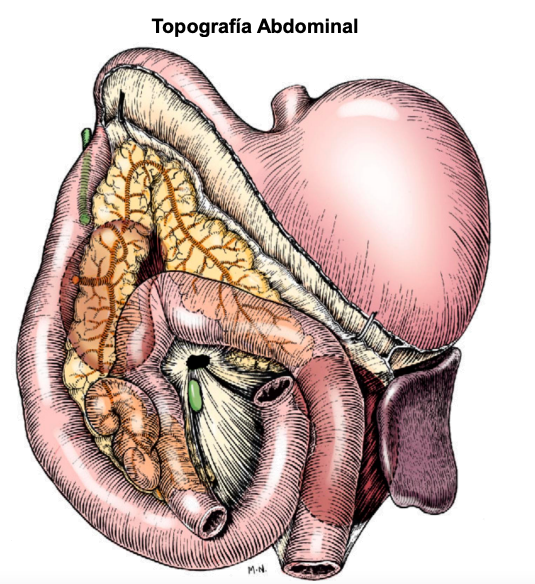

Topogradía abdominal del perro: Tac o TC del tejid blando, vista dorsal

Generalmente las imagenes de tac están espejadas

En gato el bazo siempre esta en la izquierda, el perros la cola puede estar a la derecha

esofago no se ve en radiografias. De craneal a caudal:

- Higado vesicula biliar a la derecha

- Estomago con pancreas

- Bazo (fundus a la izquierda, cola a la derecha en perros, gatos se mantiene medio-izquierdo)

- intestinos (asas intestinales) Colon ascendente derecho, descendente izquierdo